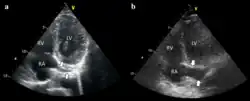

Setup for doing an ECG off the device Example of ECG off the device a) free floating in the RV b) in contact with the RV wall

Example of ECG off the device a) free floating in the RV b) in contact with the RV wall It is possible to place the lead in the coronary sinus, normal (left) dilated (right). Such placement is okay.

It is possible to place the lead in the coronary sinus, normal (left) dilated (right). Such placement is okay.